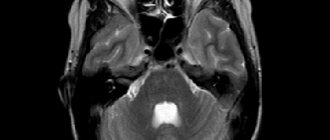

МРТ

Как и в случае с КТ, киста кажется хорошо определенной и часто соответствует сосудистой территории. Киста выстилается белым веществом, которое может или не может свидетельствовать о глиозе (это зависит от возраста, в котором произошло нарушение). Важно отметить, что киста не покрыта серым веществом, чтобы отличить их от арахноидных кист и шизенцефалии. Обычно киста видна для связи с желудочками и / или субарахноидальным пространством.

Содержимое кисты следует за CSF-сигналом на всех последовательностях:

T1: низкая интенсивность сигнала

T2: высокая интенсивность сигнала

FLAIR: подавление интенсивности сигнала

DWI: нет ограниченной диффузии